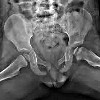

Рентгенография костей таза ребенку

Рентгенография костей таза у ребенка проводится для диагностики повреждений костей скелета этой области (переломы, переломы), дисплазии тазобедренного сустава, асимметрии костей таза, болезни Пертеса, остеосаркомы и рентгенографической оценки образования костей таза. Рентген грудной клетки костей таза дает информацию о состоянии подвздошных, седалищных и лобковых костей, лобковых и крестцово-подвздошных суставов, крестца, копчика, тазобедренных суставов и проксимальных бедренных костей. При оценке рентгенограмм учитывается наличие линии перелома, деформация контуров таза, ширина хрящевых областей при сравнении симметричных образований, смещение структур тазовой кости У ребёнка рентгенография костей таза проводится по направлению травматолога-ортопеда ребёнка.